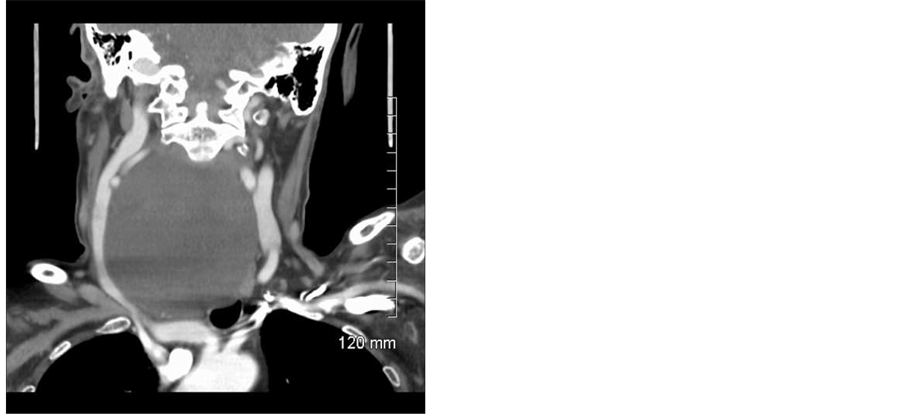

CT imaging of the neck with contrast demonstrated a complex cystic mass 8.2 × 5.6 × 10.5 cm with a 0.7 × 0.5 cm nodular and solid focus along the right lateral cyst border. The mass extended from the retropharyngeal space with mass effect on the hypopharynx, esophagus, trachea and right carotid space structures and extended into the superior mediastinum. No significant cervical lymphadenopathy was present. See Figure 1 and Figure 2.

Figure 2. CT scan with contrast of neck. This coronal slice highlights the cystic parathyroid adenomas proximity to the great vessels laterally as well as the descending trachea, superior mediastinum, right lung pleura, and arch of the aorta inferiorly.